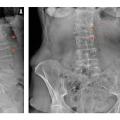

Radiographies standard

Il est indiqué de réaliser des radiographies du rachis dorso-lombaire devant des rachialgies et/ou une perte de taille supérieure ou égale à 4 cm afin de dépister une éventuelle fracture vertébrale asymptomatique (fig. 3).

Lors d’une fracture vertébrale, on recherche les signes en faveur de la nature bénigne ostéoporotique : siège de la fracture en-dessous de T3, respect du mur vertébral postérieur et de l’arc postérieur, caractère symétrique de la fracture, absence d’ostéolyse (rang B).